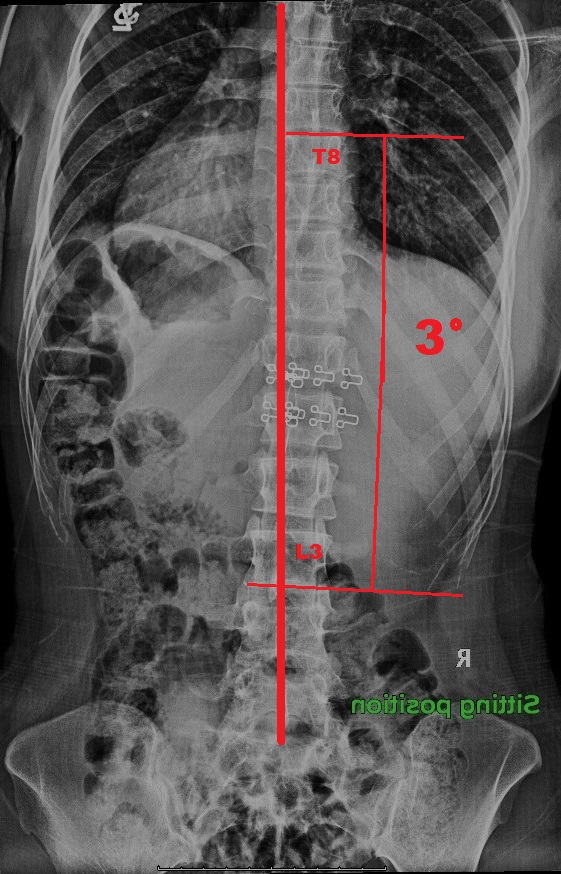

-治療期間: 14日間-

- 治療前: 側弯症カーブ 22°、痛みがあり、姿勢の悪化を感じていた

- 治療後: 側弯症カーブ 3°、痛み消失、体が軽くなり姿勢も大幅に改善

- 結果: 手術不要

Before

After